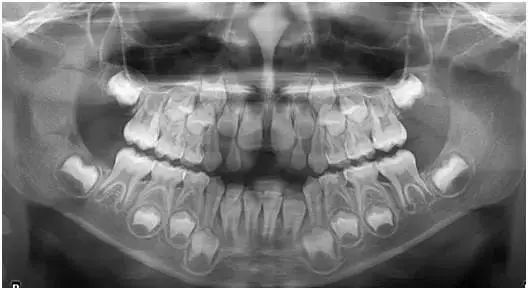

3 全景X光片

这种X光片用来观察一张胶片上的所有牙列。

X光片中显示上下颌(上下牙床)、颞下颌关节(耳朵前方的关节位)和上牙鼻窦。

如果孩子面部受伤、有正畸需求或者牙列有缺陷,通常需要拍全景X光片。全景X光片不同于其他类型的X光片,它不需要在孩子的嘴巴内放入胶片。

这种X光片对容易作呕或嘴巴比较小的孩子会有帮助。全景X光片的照射时间需要12-18秒左右,在这期间,孩子必须保持坐下或站立不动。